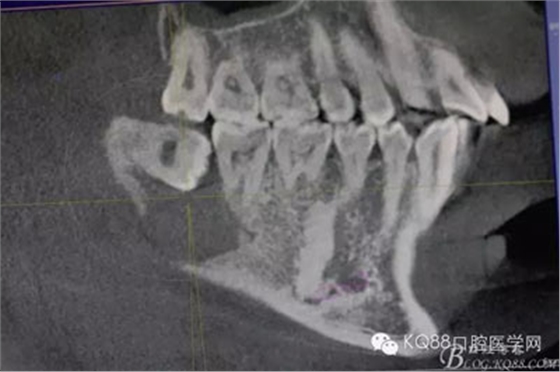

患者、常xx、男、26歲,主訴:右側(cè)下頜牙床腫痛不適數(shù)月。??茩z查:48未見(jiàn)萌出,頰側(cè)骨質(zhì)略有膨隆。捫診輕微不適,無(wú)乒乓感,牙齦色澤基本正常,探針無(wú)盲袋。全景片檢查:48埋伏水平阻生,其牙冠下方有一囊性陰影,界限清楚,大小約1.5x1.1cm。CBCT檢查:囊性病變已經(jīng)導(dǎo)致部分頰舌側(cè)骨板缺失。診斷:48埋伏阻生伴發(fā)囊性變。治療計(jì)劃:建議拔除48,并摘除下方的囊腫?;颊咄庵委熡?jì)劃,簽知情同意書。

圖2.術(shù)前的CBCT檢查:48下方頜骨橢圓形囊性陰影,下方接近下頜管。

圖3.這張重建的全景片,似乎48就漂浮在囊腔上方,由此感覺(jué)48拔除如同探囊取物一般。

圖4.三維重建也提示:48拔除難度不大